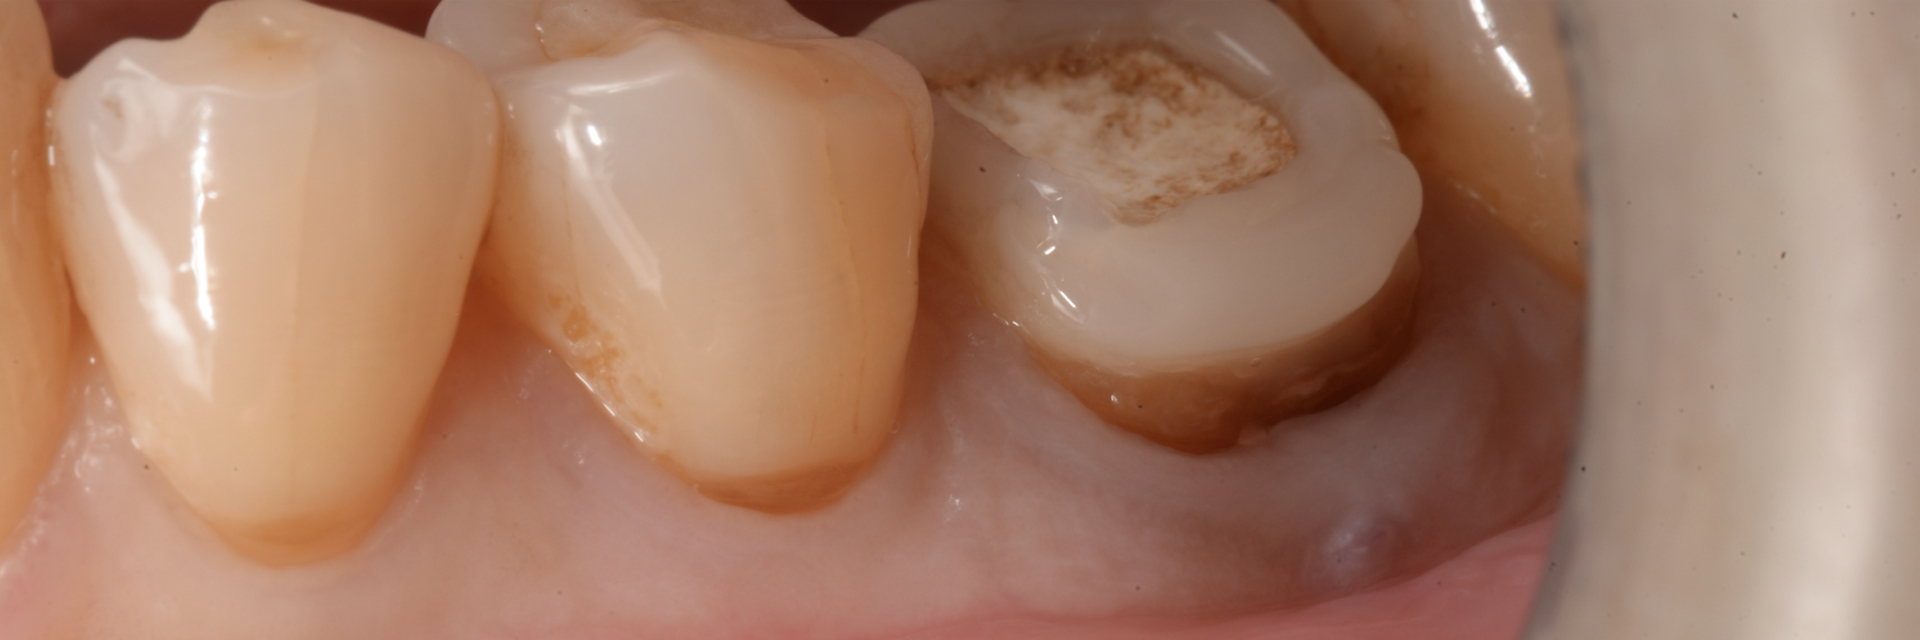

【根管治療】

| 治療内容 | ラバーダム、マイクロスコープ、 MTAを用いた精密根管治療 歯根端切除術 |

歯の保存、嚢胞の摘出